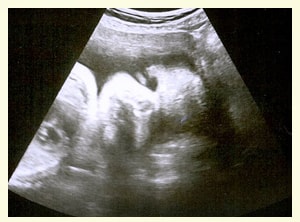

Reclaiming, Это гематома так бывает, главное верить в положительный исход 🙏😊вот мой результат, доченька ростет 30 недель в четверг будет) Изображение